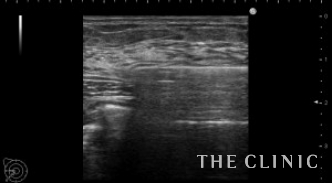

ベイザーで崩しているところです。